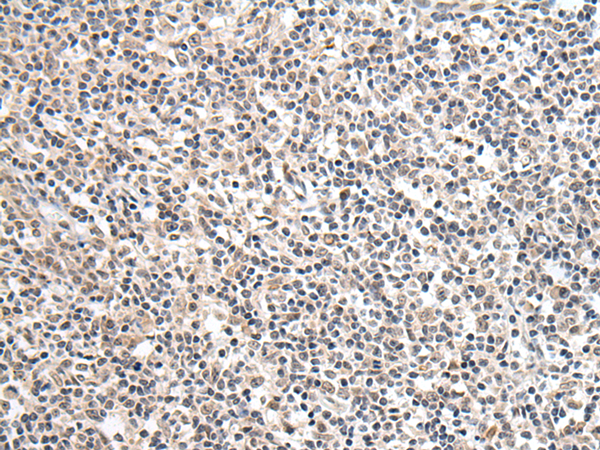

分类: 科研抗体货号: P12706别名: KHL4; DKELCHL应用: IHC反应种属: Human

分类: 科研抗体货号: P12738别名: G2L3应用: IHC反应种属: Human

分类: 科研抗体货号: P12733别名: GAS应用: IHC反应种属: Human, Mouse, Rat

分类: 科研抗体货号: P12752别名: PYHIN2; IFNGIP1应用: IHC反应种属: Human